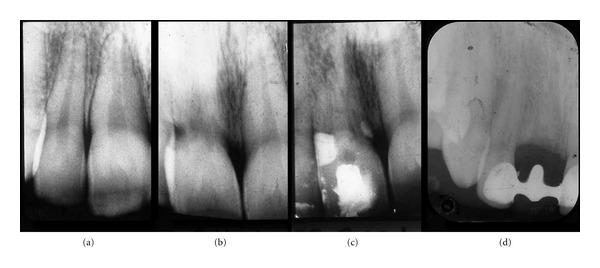

During orthodontic treatment, root resorption can occur unexplainably. No clear distinction has been made between resorption located within specific regions and resorption occurring generally in the dentition. The purpose is to present cases with idiopathic (of unknown origin) root resorption occurring regionally. Two cases of female patients, 26 and 28 years old, referred with aggressive root resorption were investigated clinically and radiographically. Anamnestic information revealed severe virus diseases during childhood, meningitis in one case and whooping cough in the other. One of the patients was treated with dental implants. Virus spreading along nerve paths is a possible explanation for the unexpected resorptions. In both cases, the resorptions began cervically. The extent of the resorption processes in the dentition followed the virus infected nerve paths and the resorption process stopped when reaching regions that were innervated differently and not infected by virus. In one case, histological examination revealed multinuclear dentinoclasts. The pattern of resorption in the two cases indicates that innervation is a factor, which under normal conditions may protect the root surface against resorption. Therefore, the normal nerve pattern is important for diagnostics and for predicting the course of severe unexpected root resorption.

在正畸治疗期间,牙根吸收可能会莫名发生。位于特定区域的吸收与牙列中普遍发生的吸收之间尚无明确区分。目的是呈现局部发生特发性(病因不明)牙根吸收的病例。对两名分别为26岁和28岁、因侵袭性牙根吸收前来就诊的女性患者进行了临床和影像学检查。既往史信息显示,两名患者童年时期均患过严重病毒疾病,其中一例患脑膜炎,另一例患百日咳。其中一名患者接受了牙种植治疗。病毒沿神经路径传播可能是意外吸收的一个解释。在这两个病例中,吸收均始于颈部。牙列中吸收过程的范围遵循病毒感染的神经路径,当到达神经支配不同且未被病毒感染的区域时,吸收过程停止。在一例病例中,组织学检查发现了多核破牙本质细胞。这两个病例中的吸收模式表明,神经支配是一个因素,在正常情况下可能保护牙根表面免受吸收。因此,正常的神经模式对于诊断和预测严重意外牙根吸收的进程很重要。